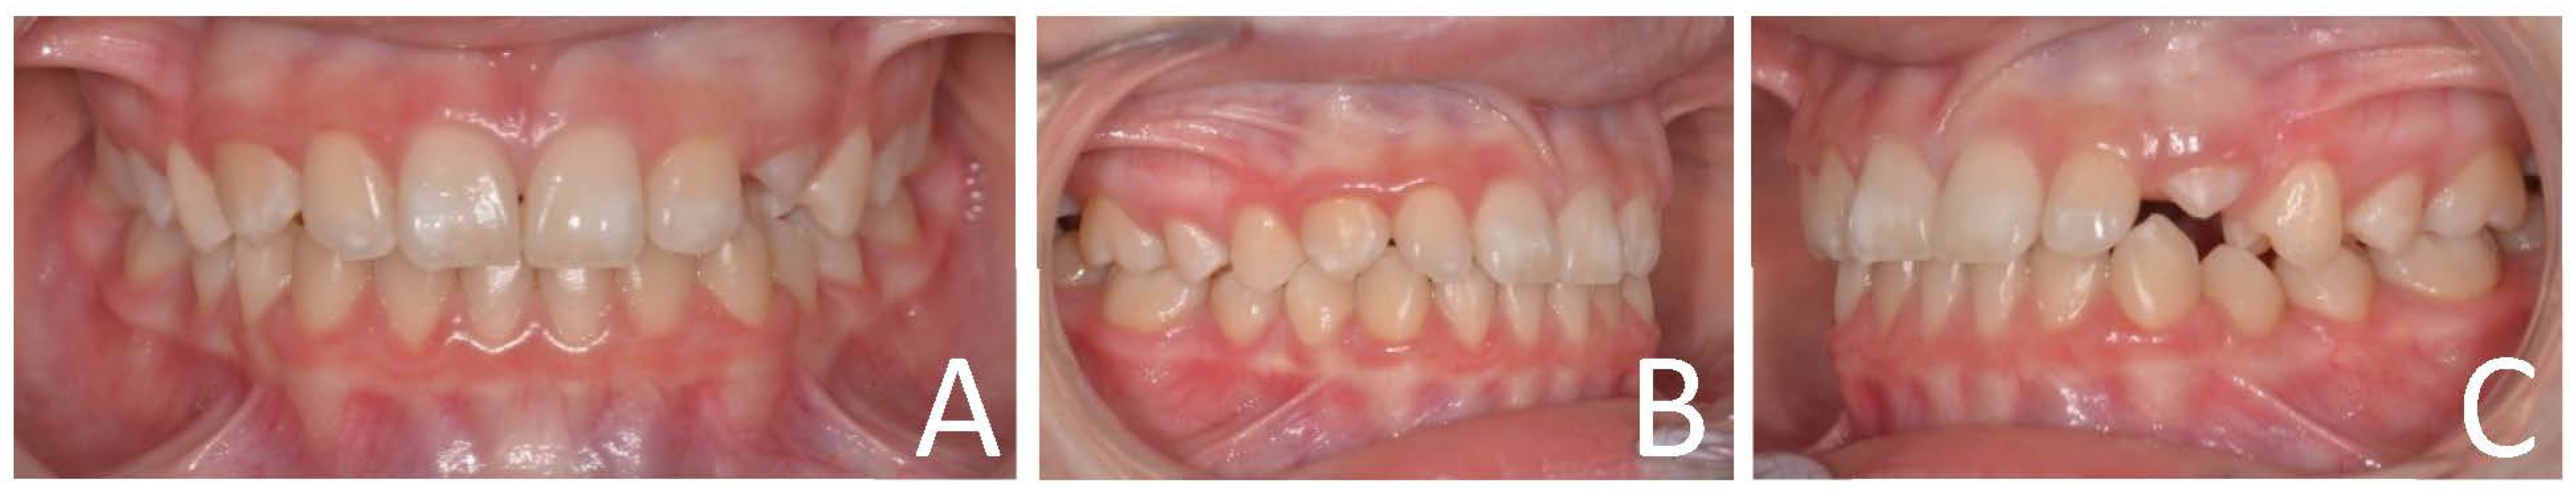

3.1. Clinical Case #1

3.2. Clinical Case #2

3.3. Clinical Case #3

3.4. Clinical Case #4